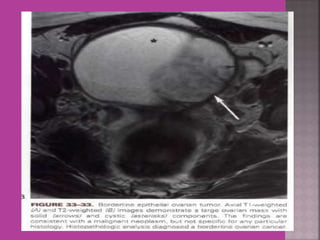

Ovarian Tumor